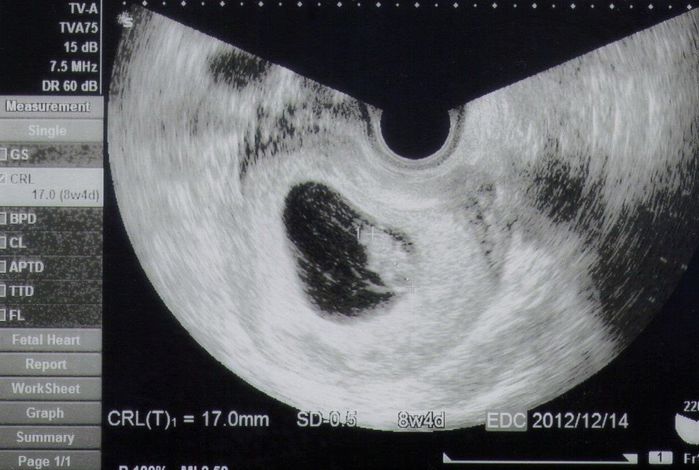

妊娠8週目のエコー写真 予定日が確定!

CRL=17㎜

真ん中の胎嚢の中に、小さな赤ちゃんが写っています。エコーで初めて赤ちゃんが手足をちょこちょこ動かしているところを見ることができ、とってもかわいかったです。ゴールデンウィークの間、体を休めて横になっていることが多かったので少し太りました。休みが終わって仕事を再開すると、気持ちが悪くて吐いてしまうことが増え、特に忙しい時に体調が悪化しやすいようでした。母の日に、夫がピンクのカーネーションをくれました。思いがけないサプライズで嬉しかったです。